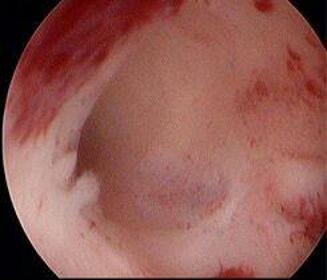

术后三个月复查宫腔正常(图)